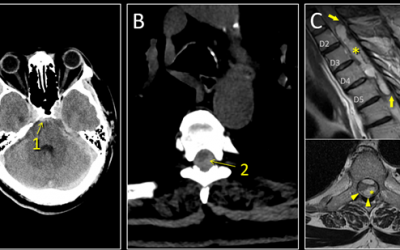

Caso del mes Marzo 2026

« Todos los casosAutores Clara de Arriba Heras, Hospital Universitario 12 de Octubre,...